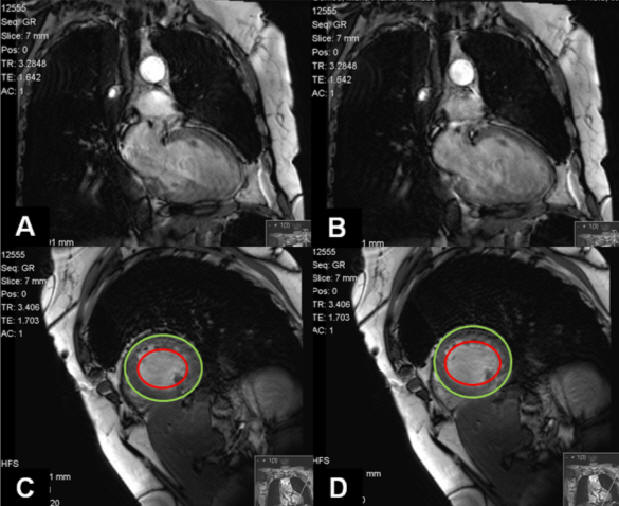

At this point we considered therapy with Infliximab to control ocular symptoms and as a way to reduce steroid use. Four months after initiating Infliximab (4 infusions), she was admitted to our department complaining of shortness of breath on exertion, severe fatigue, cough and purulent sputum. Chest X-ray was similar to previous exams. Laboratory tests presented CRP 2,4mg/dL and PaO2=54,2mmHg (room air). She was given antibiotics and in spite of resolution of cough and sputum, dyspnea and respiratory failure persisted. At this time NT-proBNP was determined (4421 mg/dL) and repeated echocardiogram demonstrating a dilated left ventricle (LV), generalized hypokinesis, a global systolic dysfunction (ejection fraction of 19%) and diastolic dysfunction. She underwent coronariography revealing coronary arteries without lesions and mean pulmonary artery pressure of 33mmHg. A cardiac MRI (Figure 1) was performed indicating an important compromise of LV function without wall edema or delayed-enhancement that could be suggestive of cardiac sarcoidosis involvement.

Figure 1. Cardiac MRI demonstrates important compromise of LV function. (A and C) Cardiac systole seen by closed mitral leaflets. (B and D) Cardiac diastole seen by open mitral leaflets. The area comprehended between the two circles represents myocardium thickness. There’s not a significant variation of this area when in systole or diastole.